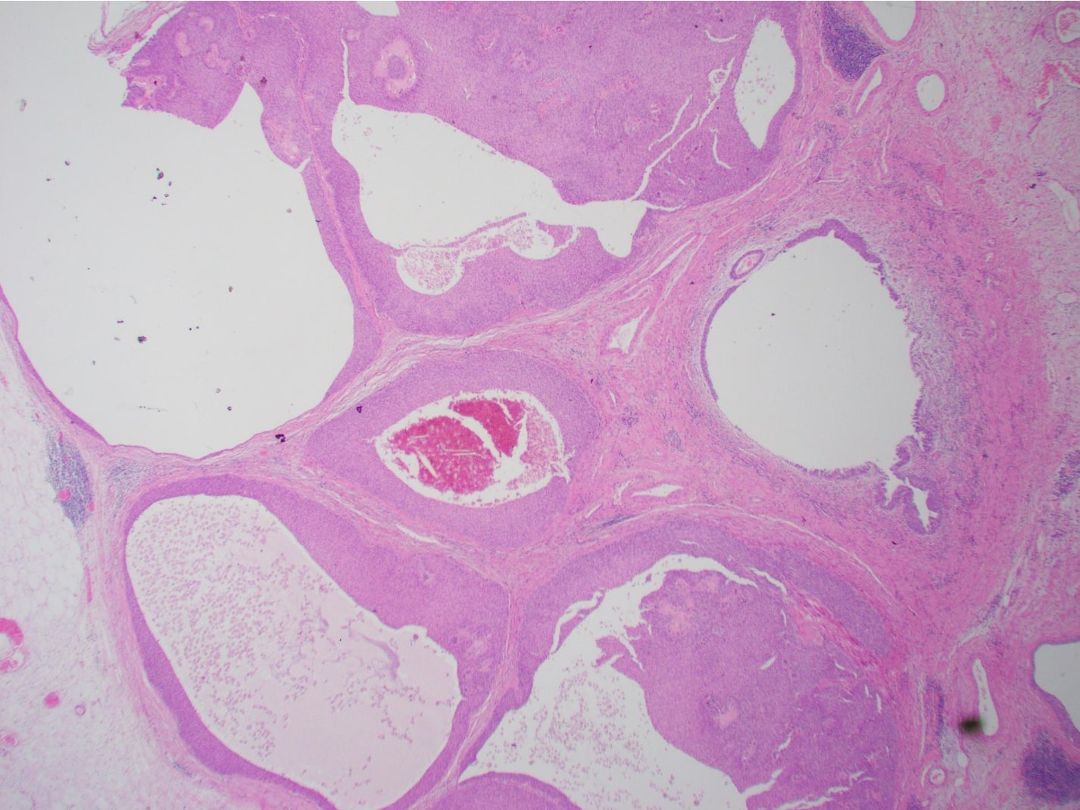

The patient underwent robot-assisted left nephroureterectomy (Figure 2). Histopathology revealed multicystic, non-invasive, low-grade urothelial carcinoma in the periureteric space, surrounding but not invading the ureter, confirming the diagnosis of extra-ureteric urothelial carcinoma—a presentation never previously described in the literature (Figure 3).

Figure 3 Histopathology demonstrating multicystic urothelial carcinoma without ureteric invasion